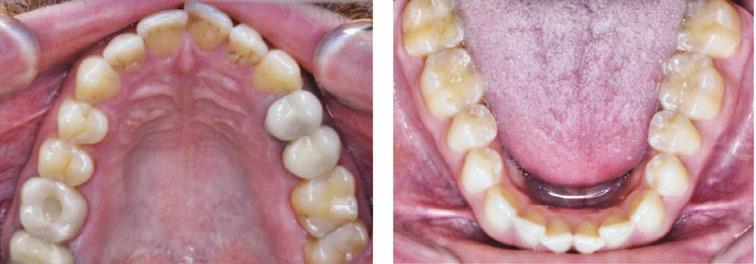

tan was referred to my office by a TMD specialist. His chief complaints were he could not chew or open his mouth without pain. It seemed the less he chewed, the more pain he experienced. As a result, an Orofacial Myofunctional Therapy (OMT) program was created to help support his muscles of the TMJ and craniofacial respiratory complex. He used his splint as instructed by his specialist. However, his anterior open bite widened, and his teeth became more misaligned over time.

Stan was a 28-year-old male in a lot of pain. He had just come from his TMJ specialist where he received an oral orthotic splint to relieve his discomfort. He told me it all started after a long dental appointment where he received a root canal and a new crown on the upper right. After this procedure, his jaws felt tight so he gave it a good stretch by opening very wide. He heard a rip and a crunch. Opening his mouth was never the same after that. He presented with a set of symptoms: TMD muscle pain, he could no longer chew his food without pain (food had to be the soft consistency of tofu), daytime clenching and night time grinding of his teeth. In addition, he had daily headaches and ear ringing. He could not open his mouth very wide without experiencing sharp pain. He took acetaminophen for his discomfort and zolpidem nightly to help him fall asleep easier.

Upon closer examination, there were contributing factors that led to his discomfort. Stan had been a stomach/face sleeper for years. He also bit his nails since childhood, had a smoking habit from his youth, and he was prone to ear infections. He had moderate tongue and buccal ties, obligate mouth breathing, aggravated by a deviated septum, narrow nares, low tongue resting posture, an

anterior open bite, a lower jaw that deviated upon opening, and bouts of acid reflux.

An orofacial therapy program was created to allow his tongue to give better support and function to his oral structures, especially the TMJ joint. When the tongue naturally rests in the palate, it removes the unwanted pressure off of the TMJ. As part of the course of his therapy, focus was made to reeducate his breathing to make his nose the primary way he breathes. Optimal breathing rate for an adult is slower than for a child. Good nasal breathing during the day supports good nasal breathing during the night for optimal sleep. When the tongue rests in the palate, it impacts facial development especially for children who are still growing. An adult, for example, like our friend Stan, the progress made is gradual but more likely to last a lifetime. Generally, therapy starts out once a week for about 2-3 months. Then therapy progresses to every other week for 2-3 months, and then changes to once a month for about 5 months for the rest of the year. The exercises are done a minimum of 2 times everyday. These exercises are designed to strengthen and tone the orofacial muscles, building brand new neuromuscular function. When the muscles of the face are well developed, it may favorably impact appearance and the overall integrity of the facial structures. The muscles of the face also include the tongue, lips, cheeks and neck. Although the therapy program is typically only a year, Stan really liked how good he felt and decided to continue with some of the exercises to this day. From the photos you can see how much the program has impacted his health and well-being.

During his therapy, there was a discussion about the possible benefits he may receive from having his jaws expanded, making more room for his tongue, then to be followed by a tongue and buccal frenums release. His intermolar width is 34 mm, and his intercanine width is 25 mm. I feel any expansion has a potential benefit.

To document any initial assessment, the midpoint of therapy, and when therapy has ended, it is important to take detailed photos, videos, plus full measurements of the face and teeth. This makes it possible to compare results while showing that your therapy works based on the evidence you gathered before, during, and after treatment.